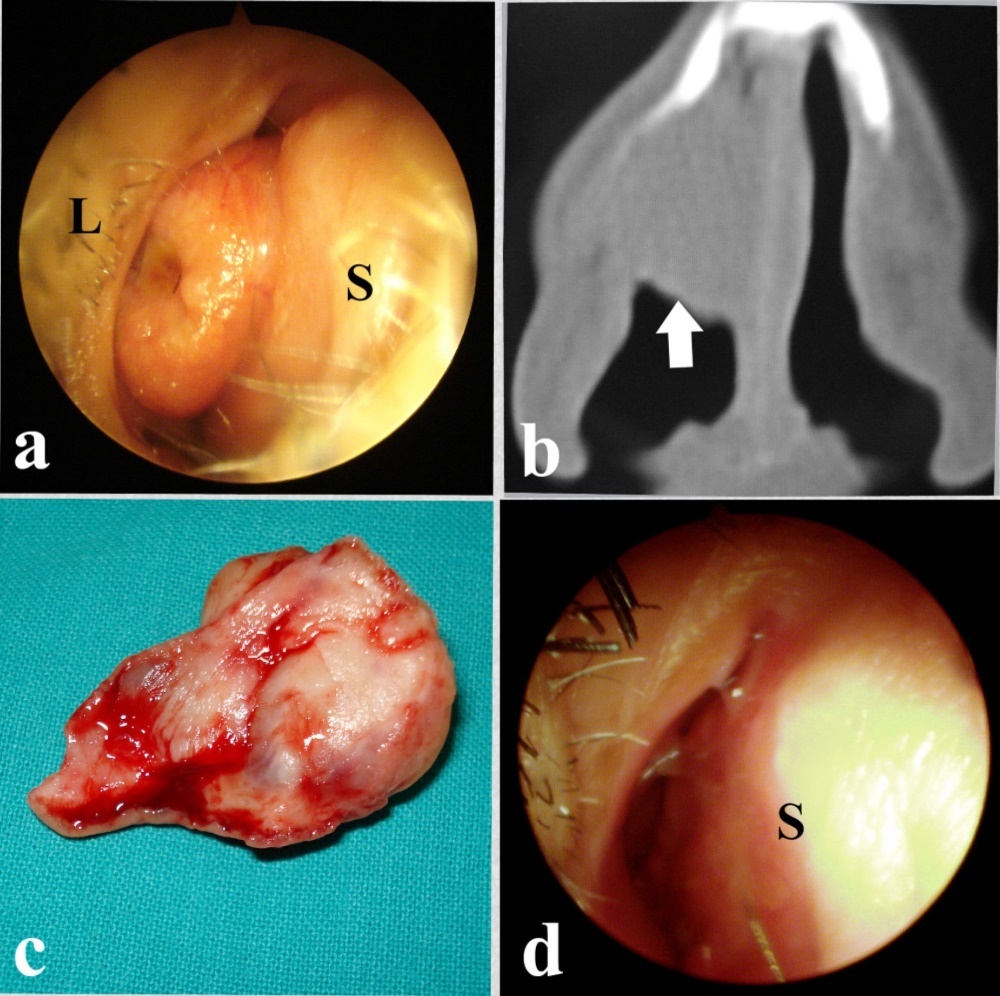

Endoscopic examination, in all cases, revealed a well-defined moderately firm mass that did not bleed on gentle touch (Figure 1a). CT scans showed a well-defined soft tissue mass with a smooth border. The mass expanded the external nose in 3 cases (Figure 1b).

In all cases, the mass was excised endoscopically under general hypotensive anesthesia. During surgery, the tumor was found to be attached to the nasal septum in 7 cases and to the lateral nasal wall in front of the middle turbinate in a single case .The tumor was excised together with the underlying mucosa / mucoperichondrium leaving a bare area corresponding to the size of the tumor (Figure 1c). The postoperative course was uneventful and no complications were encountered. The bare areas healed completely within few weeks (Figure 1d).

Figure 1.a-Endoscopic view of the adenoma. S: Septum, L: Lateral wall, b-Coronal CT scan showing the adenoma (arrow), c-The excised adenoma, d-Complete healing of the septum (S).